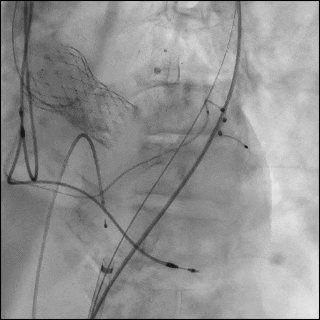

随后采用23 mm TRUE 球囊对未完全扩张的 S3UR 瓣膜行后扩张(图6D,视频9)。后TEE提示瓣膜位置良好,无瓣周漏(PVL)。

将16F鞘管回撤至左髂外动脉水平,并植入一枚8×59mm VBX 覆膜支架用以修复左侧髂总动脉夹层(图6E,视频10和11)。左股动脉穿刺口采用7×50mm Viabahn 覆膜支架进行封闭(图6F,视频12)。最终造影示无造影剂外渗,血流通畅(视频13)。

术后第1天TTE显示左室射血分数40%,无跨瓣反流,轻微瓣周漏,平均跨瓣压差6mmHg,有效瓣口面积1.78 cm²。术后恢复顺利,于术后第11天出院。

30天随访时患者NYHA Ⅱ级。TTE显示峰值流速1.5 m/s,平均压差6mmHg,有效瓣口面积1.43cm²,无跨瓣反流,仅轻度瓣周漏。